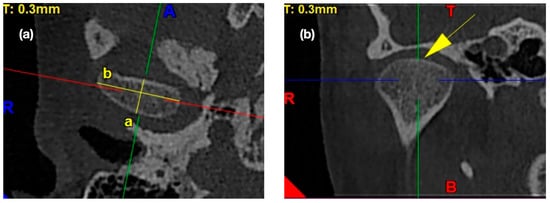

2.4.1. Morphology of the Mandibular Condyle

2.4.4. Assessment of the Anterior, Posterior, and Superior Joint Spaces

2.4.5. Assessment of the Sagittal Position of the Condyle

- P—posterior joint space,

- A—anterior joint space.